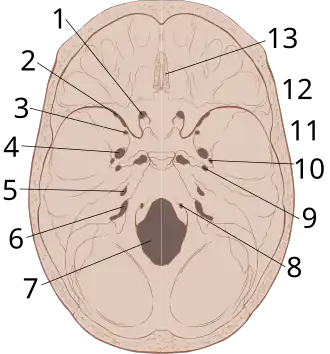

The interior of the skull has sharp ridges by which a moving brain can be injured.

Epidural hematoma commonly results from a blow to the side (temporal bone) of the head. The pterion region, which overlies the middle meningeal artery, is relatively weak and prone to injury.[10] Only 20 to 30% of epidural hematomas occur outside the region of the temporal bone.[11] The brain may be injured by prominences on the inside of the skull as it scrapes past them. Epidural hematoma is usually found on the same side of the brain that was impacted by the blow, but on very rare occasions it can be due to a contrecoup injury.[12]